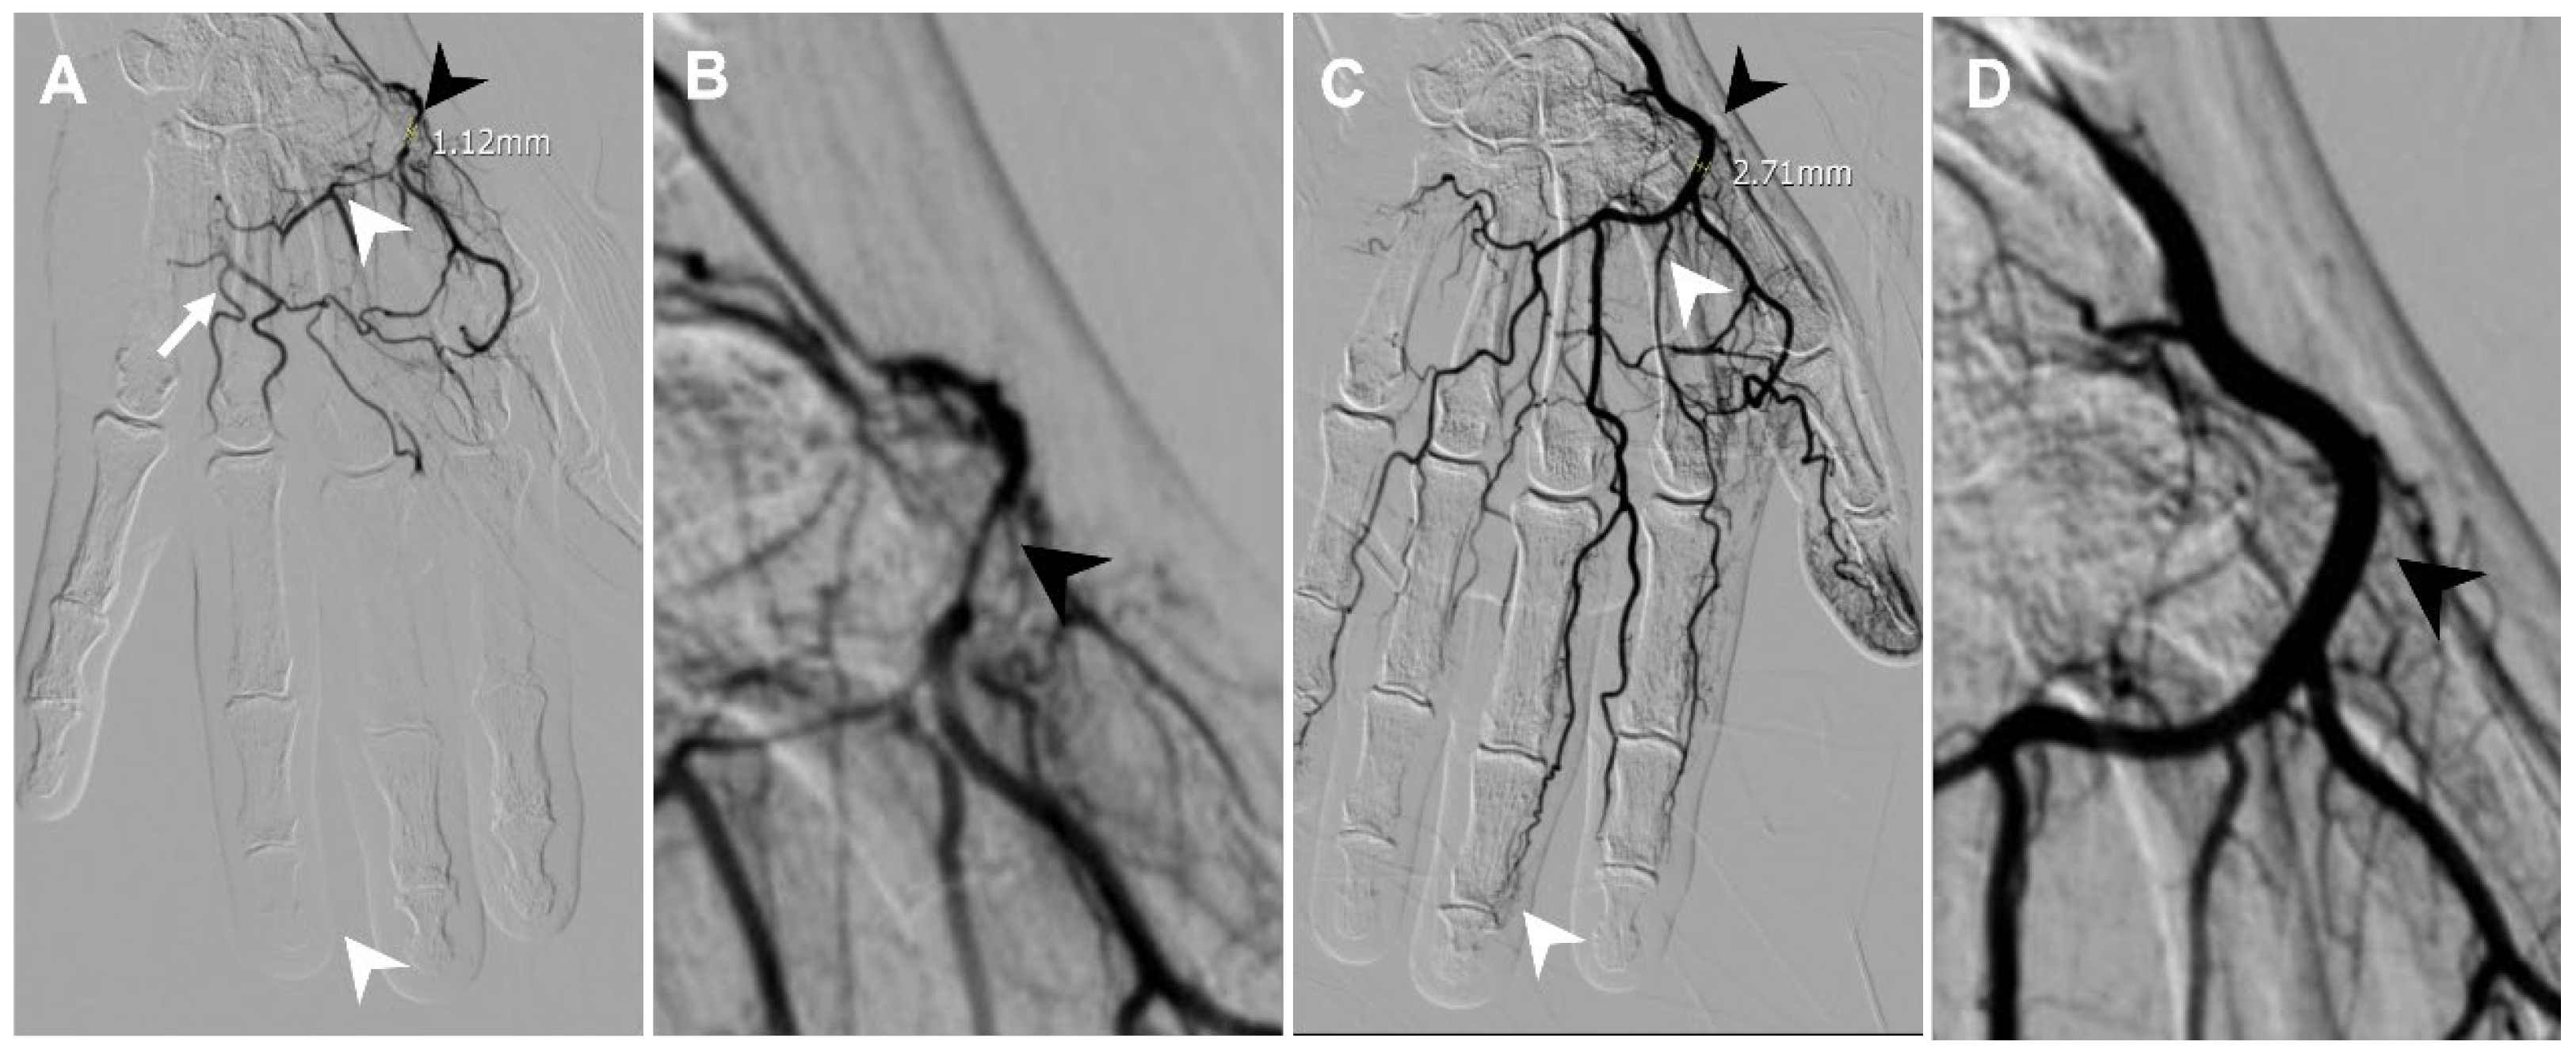

3.3. Triangular Fibrocartilage Complex (TFCC) Tear

| Finger OA | Radial artery | 1.12 | 2.71 |